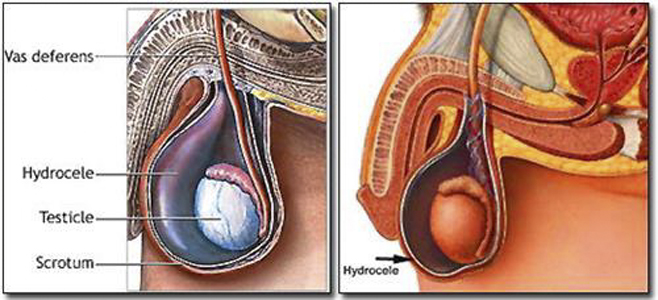

A:睪丸鞘膜積液的危害,包括鞘膜積液進行性的進展加重,可能會導致患者出現疼痛、墜脹,甚至可以影響睪丸的血運和溫度,引起睪丸的萎縮,甚至雙側積液可以影響生育能力。通常睪丸積液可能與創傷、炎症,或者心功能不全、腹水等相關。在臨床上對於睪丸鞘膜積液……

A:陰囊睪丸鞘膜積液通常主要的治療是採用手術治療,但是對於小兒、嬰幼兒的鞘膜積液,有自然消退的可能性,通常可以暫時無須治療。對於成人較小的鞘膜積液,也可以採取保守觀察的方法。對於急性炎症引起的鞘膜積液、外傷性鞘膜積液,可以自行消退,需要控制原發……

A:正常情況下睪丸鞘膜腔內是可以有一些液體的,保證睪丸在陰囊內具有一定的活動範圍,隨著睪丸陰囊鞘膜腔的液體增加,我們稱之為鞘膜積液。鞘膜積液可以分成睪丸鞘膜積液、精索鞘膜積液或者混合型的鞘膜積液,以及交通性鞘膜積液和嬰幼兒的鞘膜積液,鞘膜積液在……